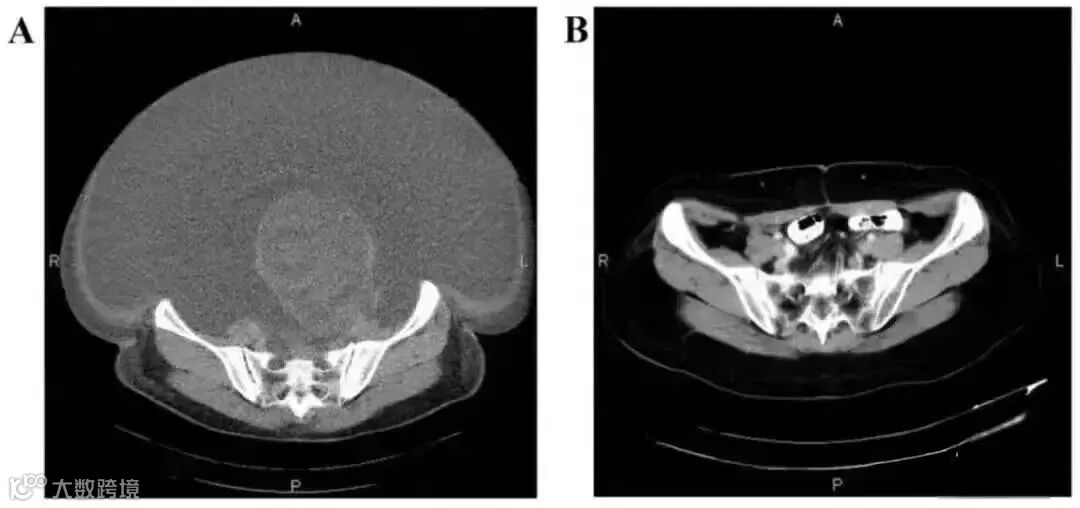

案例2:国内一名60岁的卵巢癌晚期患者,在接受了体外扩增,高度活化的同种异体NK细胞的治疗后,CA125水平从11270降到580,所有腹水都消失了。此外,CT扫描的肿块体积减小,并且没有出现副作用。